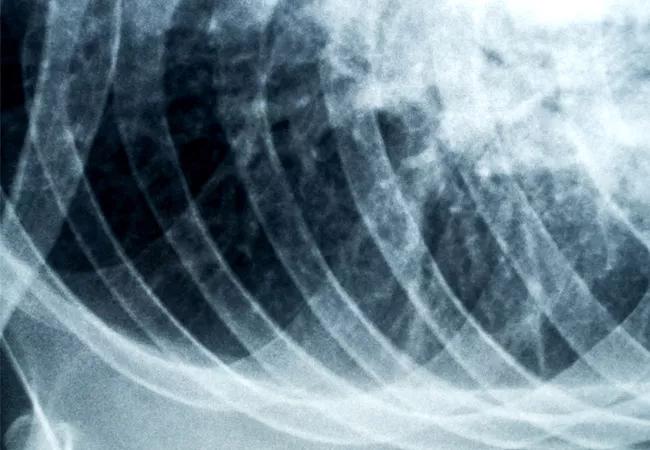

Improving Outcomes for Lung Transplant Candidates with Cystic Fibrosis

With the advent of improved diagnostic and treatment modalities, patients with cystic fibrosis (CF) are living longer than ever. These patients face irreversible, end-stage pulmonary disease, such as CF-related bronchiectasis and suppurative lung infections, and eventually need lung transplantation.